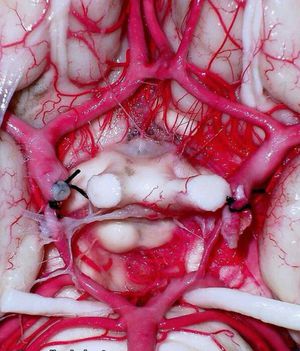

#circle of willis